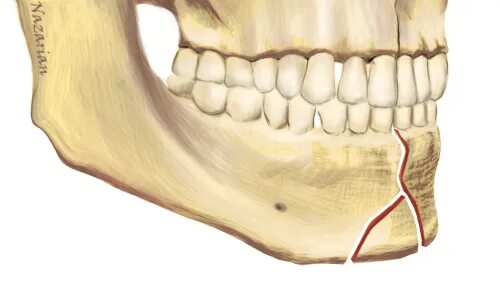

Переломы челюстей студфайл